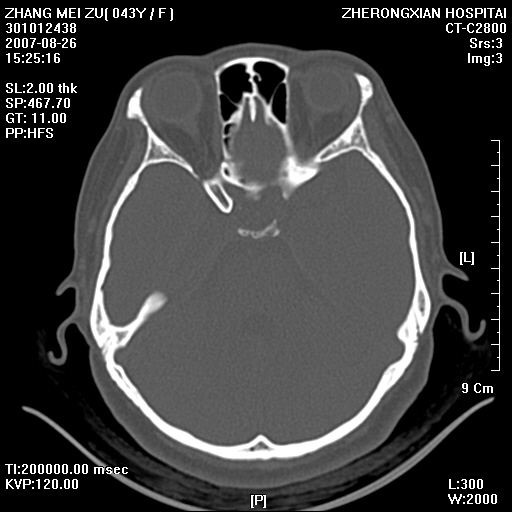

标题: CT9512:F43Y,是肉芽肿还是胆脂瘤?诊断报告该如何出? [打印本页]

标题: CT9512:F43Y,是肉芽肿还是胆脂瘤?诊断报告该如何出?

右耳硬化性乳突炎并胆脂瘤形成

右耳硬化性乳突炎并鼓窦入口胆脂瘤形成,左侧乳突炎

右侧中耳乳突炎,伴鼓窦入口胆脂瘤形成.

从发病部位及骨质破坏应该考虑是获得性胆脂瘤

典型胆脂瘤,从上鼓室,乳突窦入口到乳突窦有明显光滑的骨质破坏和软组织结节均为胆脂瘤特点.而肉芽肿对骨质的破坏是轻微的.值得关注的是乳突后壁被破坏只剩薄薄的一层,如果再不尽快治疗,胆脂瘤如果突破其后壁即可能形成耳源性脑脓肿了.